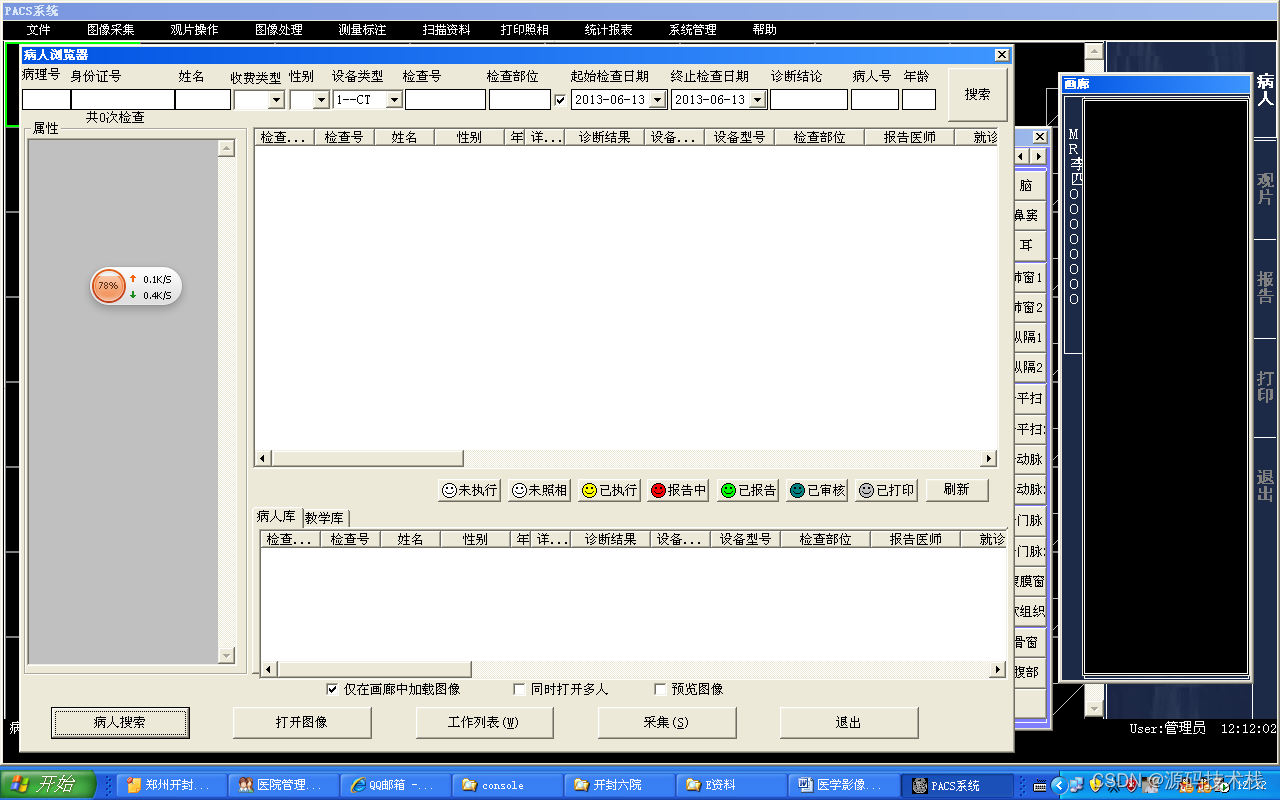

影像管理和查询功能

系统采用数据库方式管理影像及数据;

支持多种方式查询患者信息,包括患者姓名、诊疗卡号、住院号、检查号、ID号、检查科室、检查医生和影像设备等;

支持在数据库中建立患者ID号与影像内容及存储位置对照表;

支持将病人每次检查及体检的资料与图像归档;

支持按时间顺序对光盘资料进行编号归档,便于调阅及传送;

支持影像 调出、转存、删除和图像迁移功能。